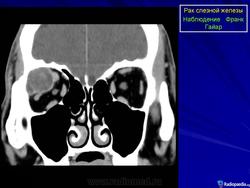

Диагноз устанавливают только после гистологического исследования. Предположительный диагноз может быть установлен на основании анализа клинических симптомов и результатов инструментального исследования. При рентгенографии на фоне увеличенной в размерах орбиты выявляются участки костной деструкции, чаще в верхненаружной, верхней и наружной стенках орбиты. Компьютерная томография позволяет определить протяженность тени опухоли, неравномерность ее краев, распространение в прилежащие экстраокулярные мышцы и неравномерность контуров костной стенки орбиты или ее полное разрушение, а ультразвуковое исследование — лишь наличие тени опухоли и ее плотность. Радиосцинтиграмма орбиты при аденокарциноме характеризуется увеличением коэффициента асимметрии, свойственного злокачественным опухолям. Информативна дистанционная термография, особенно с сахарной нагрузкой. Уточнить диагноз помогает дооперационная тонкоигольная аспирационная биопсия.